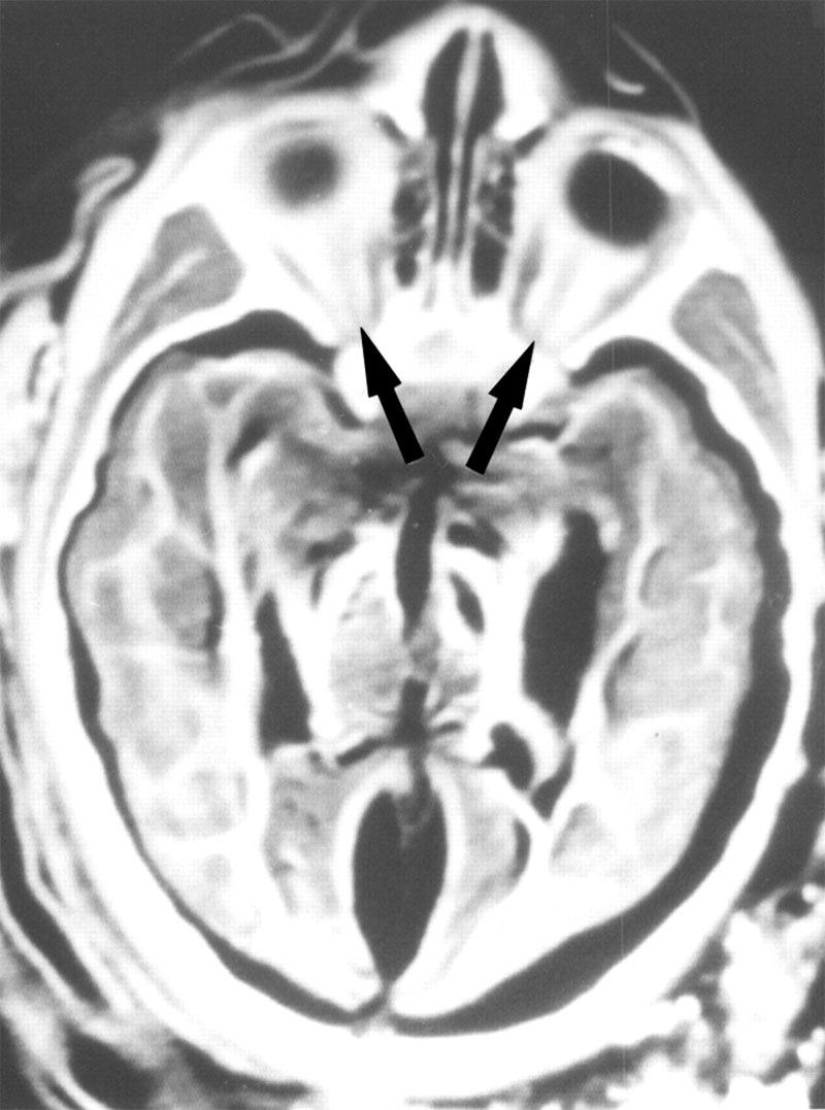

Una radiografía del cerebro de una niña de 6 años mostró que fue alcanzada por un rayo. Sus órbitas con ojos, nervios ópticos (flechas) y músculos visuales se muestran aquí.